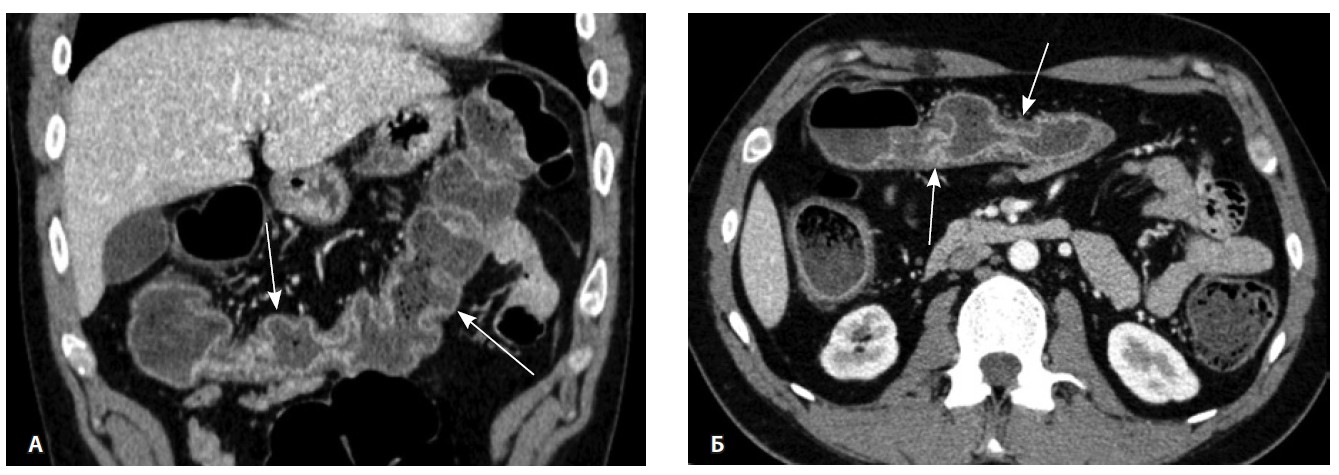

Назначена ГИБТ адалимумабом (препарат Хумира) по стандартной схеме 160 мг п/к (неделя 0), 80 мг п/к (неделя 2) с последующим плановым поддерживающим режимом 40 мг п/к каждые 2 недели. Через 9 месяцев установлена эндоскопическая ремиссия, однако сохранялась концентрация фекального кальпротектина более 2000 мкг/г. Через год жалобы возобновились, тогда же впервые была выявлена задняя анальная трещина. Выполнена магнитно-резонансная энтерография, обнаружены воспалительные изменения, характерные для БК (рис. 2 и 3).

Рис. 3. Магнитно-резонансная энтерография, Т1-взвешенное изображение после внутривенного контрастного усиления (гадобутрол, 5 мл): А – фронтальная проекция, Б – аксиальная проекция. Наблюдается выраженное усиление интенсивности сигнала от восходящего отдела ободочной кишки (стрелка), усиление сигнала от окружающей клетчатки (пунктирная стрелка)